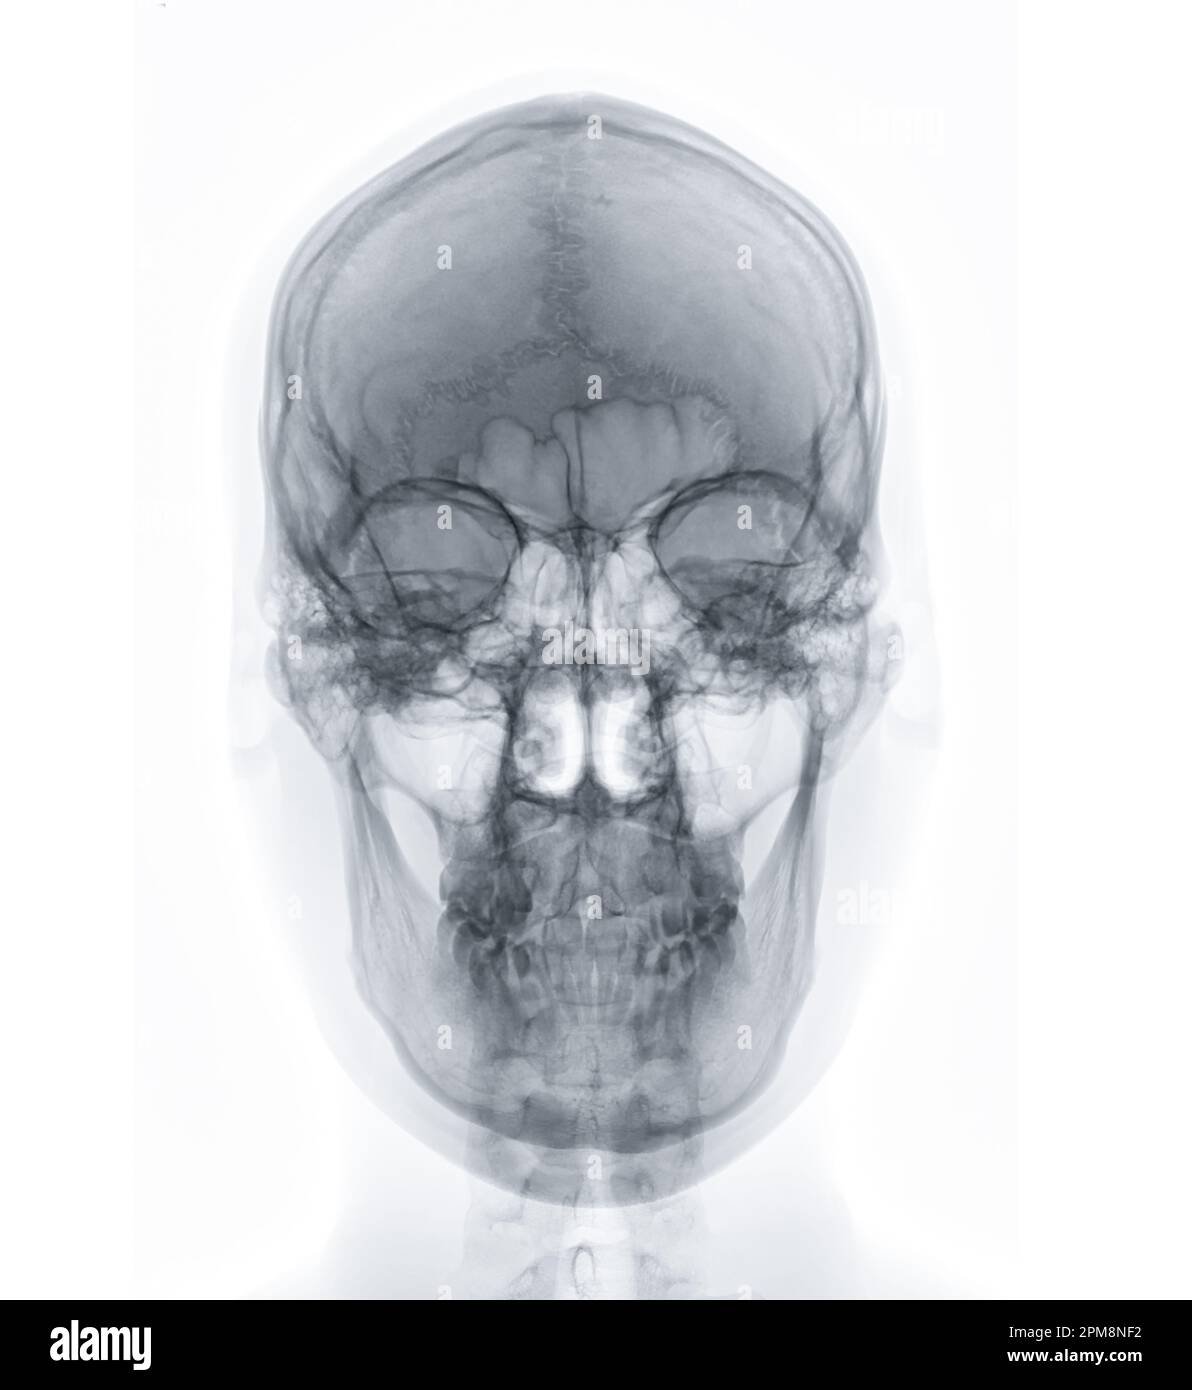

Prepare to be captivated by List, a showcase of real human skull front view black and white imagery powered by ieltschampions.edu.vn. More related visuals are below.

real human skull front view black and white

Posts: real human skull front view black and white